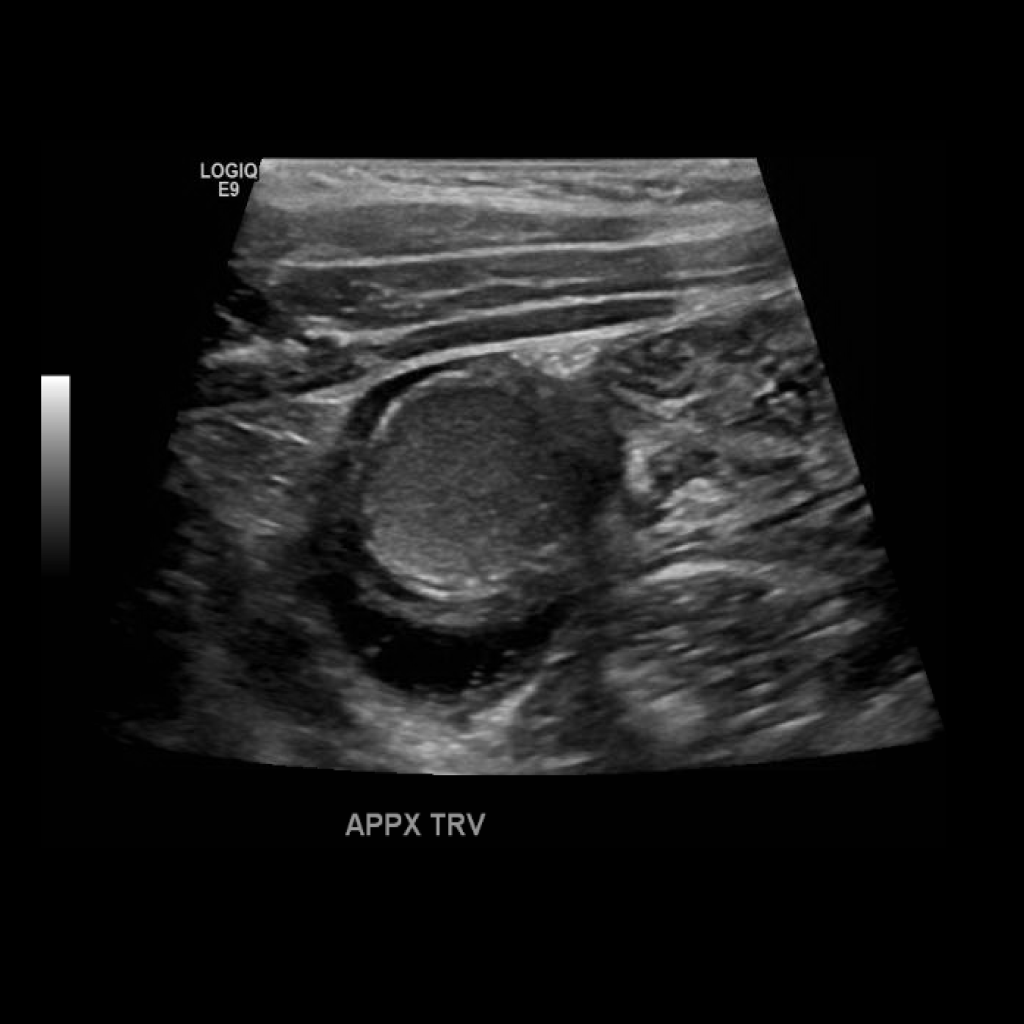

Appendicitis 12

0.9 cm positive appendicitis, with peripheral free fluid, and fat stranding.